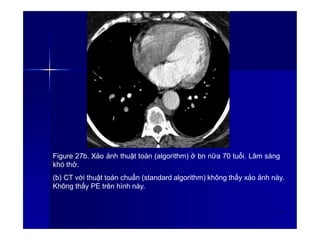

Figure 27a. Xảo ảnh thuật toán (algorithm) ở bn nữa 70 tuổi. Lâm sàng

khó thở.

(a) CT cho thấy có tăng quang ngoài rìa các mạch máu giống hư PE

cấp. (mũi tên). Dấu hiệu này thường thấy khi ta xem lại hình bằng các

cửa sổ trung thất hay cửa sổ phổi chuyên về thuyên tắc (nghĩa là có áp

dụng thuật toán trong tái tạo hình ảnh) thấy có vòng sáng bright quanh

động mạch đặc biệt khi có kèm với xảo ảnh dòng chảy.

35

Figure 27b. Xảo ảnh thuật toán (algorithm) ở bn nữa 70 tuổi. Lâm sàng

(b) CT với thuật toán chuẩn (standard algorithm) không thấy xảo ảnh này.

Không thấy PE trên hình này.

36